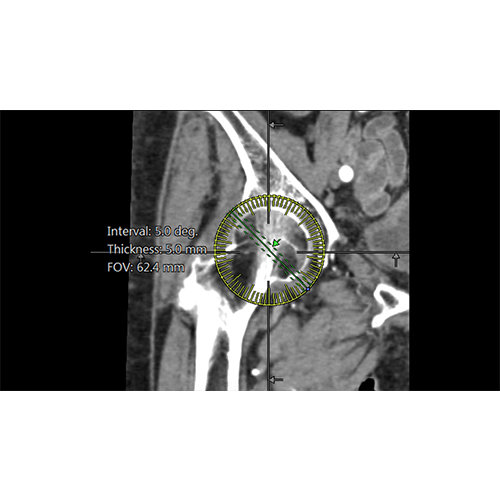

View X-Ray CT & MRI Scans Fast and Easily

Designed for surgeons, Pro Surgical 3D makes it easy to view patient scans quickly. Pro Surgical 3D facilitates the optimal 3D treatment and assessment workflows based on X-ray CT and MRI scans – and best of all, it’s FREE!

Performs 3D reconstruction and volume rendering.

Multi-planar slicing.

Oblique slicing.